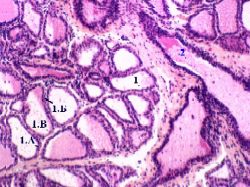

В. Концевые отделы: характеристика компонентов

1. а) Стенка альвеолы образована одним слоем лактоцитов (1.А) -

клеток кубической формы,

имеющих круглые ядра

и лежащих на базальной мембране.

б) Местами в стенке находятся и миоэпителиальные клетки (1.Б): они

окружают альвеолу снаружи, охватывая её своими отростками,

и отличаются палочковидными ядрами.

в) В просвете альвеол - капли секрета (1.В).

б) Большое увеличение

2. а) Клетки, образующие

млечный альвеолярный ход (2),

тоже лежат в один слой и,

видимо, тоже способны к секреции - но в меньшей степени.

б) Поэтому

в них меньше цитоплазмы,

отчего ядра клеток расположены гораздо ближе друг к другу.

в) По данному признаку млечные альвеолярные ходы (2) можно отличить от альвеол (1).